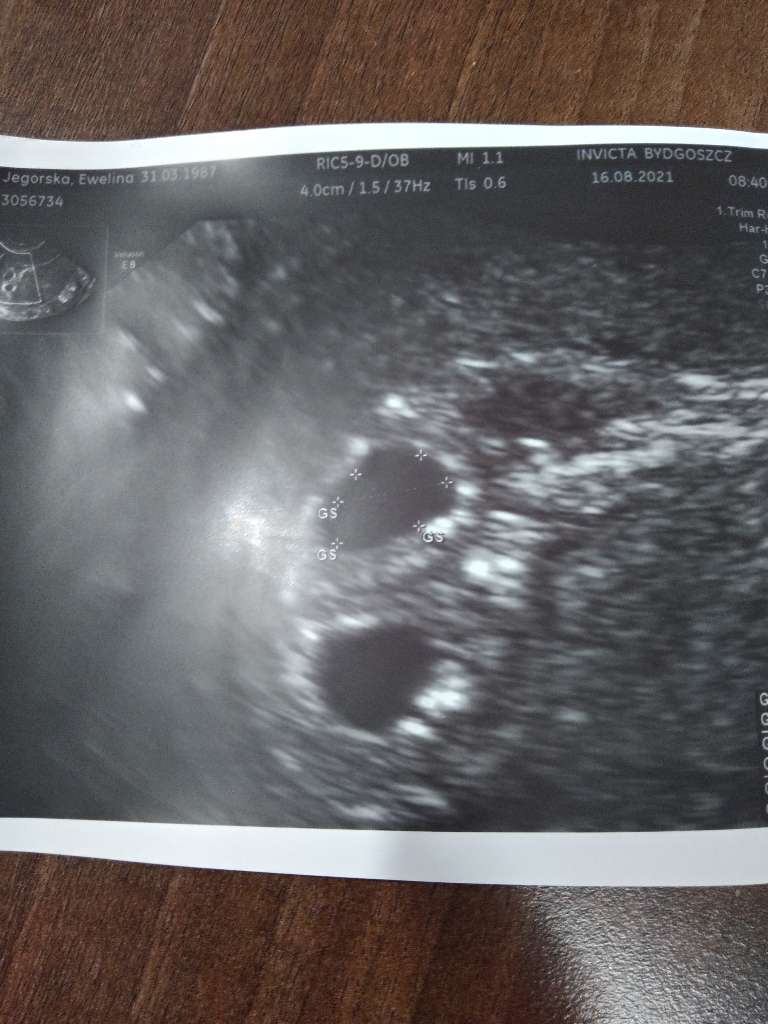

Załączniki

• 654a66df-dcd0-443d-b0ea-46008248bf66.jpg

654a66df-dcd0-443d-b0ea-46008248bf66.jpg

67,3 KB · Wyświetleń: 133